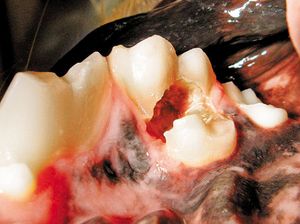

Extractions of teeth in dogs and cats are commonly categorized as simple or surgical, Surgical extractions involve periodontal flaps and the removal of bone to expose tooth roots. Simple extractions in some cases are not always simple as their name implies. Fractures during extraction may require surgical methods to complete the procedure.

Correct management of periodontal patients in veterinary practice demands a thorough understanding of veterinary dental radiographic anatomy, periodontal probing and many times open evaluation and direct visualization of diseased areas. Stage III periodontal disease in particular requires advanced skills and familiarization with periodontal pathophysiology to make decisions to attempt to grow new supportive tissue adjacent to compromised teeth or extract them.